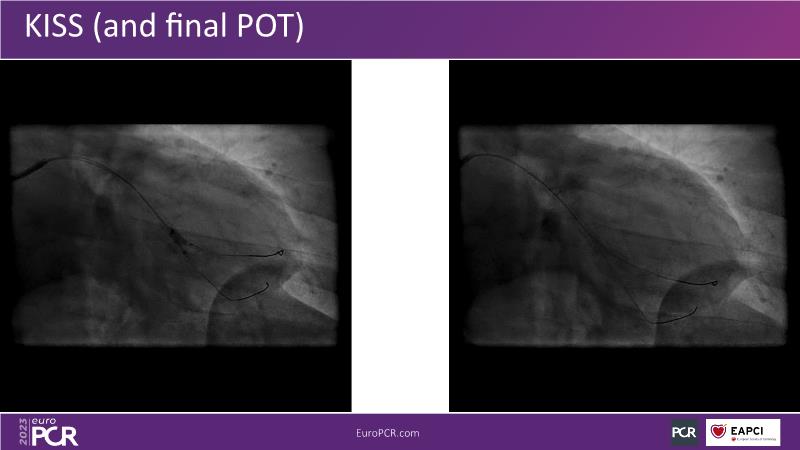

In this session, watch a case of intravascular imaging guided LM PCI from the ROLEX Registry, learn more about EBC MAIN 3-year results, see a case presentation with use of FFRangio, find out more about the KISS Trial, and follow the debates about all these learnings.

- To discuss about side branch protection strategies via practical cases and learnings from the KISS trial